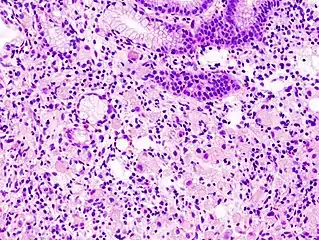

Signet ring cell, as seen in a case of colon adenocarcinoma with mucinous features, showing a tumor cell with a vacuole of mucin. H&E stain.

In histology, a signet ring cell is a cell with a large vacuole. The malignant type is seen predominantly in carcinomas. Signet ring cells are most frequently associated with stomach cancer,[1] but can arise from any number of tissues including the prostate,[2] bladder, gallbladder,[3] breast, colon,[4] ovarian stroma and testis.[5]

The name of the cell comes from its appearance; signet ring cells resemble signet rings. They contain a large amount of mucin, which pushes the nucleus to the cell periphery. The pool of mucin in a signet ring cell mimics the appearance of a finger hole and the nucleus mimics the appearance of the face of the ring in profile.